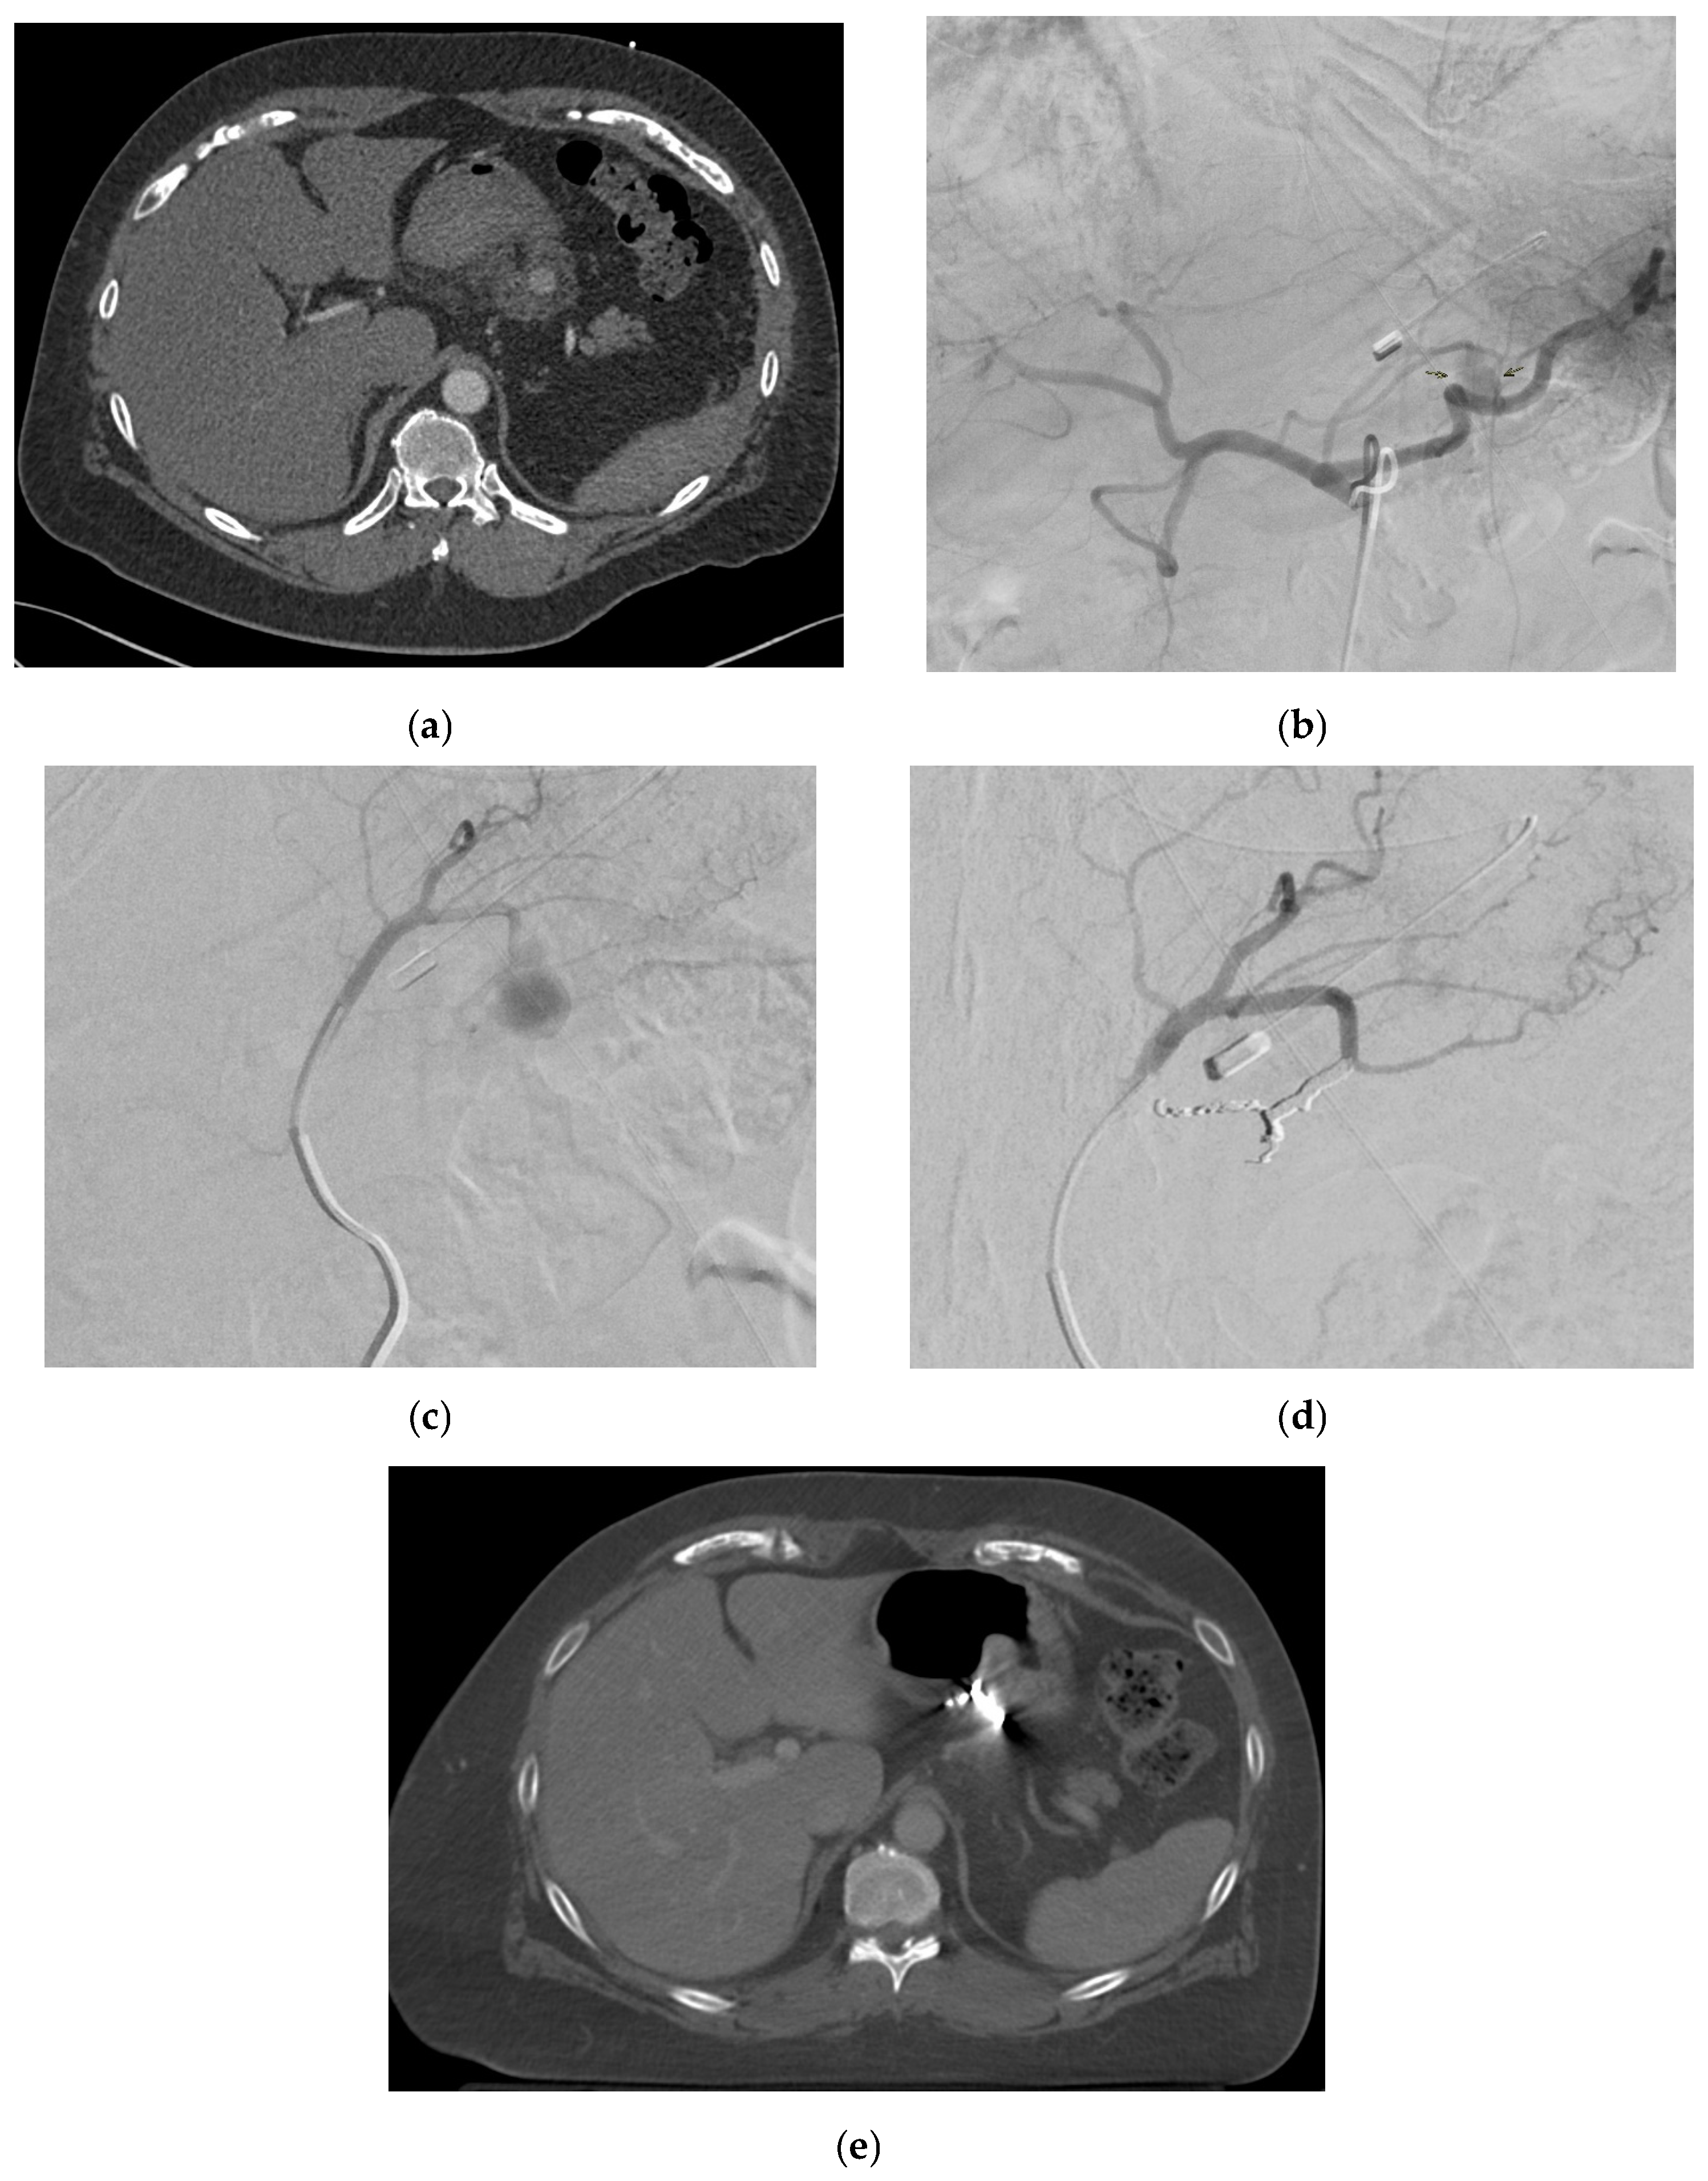

2.4. Splenic Artery

2.4.4. Diagnosis

2.4.5. Management